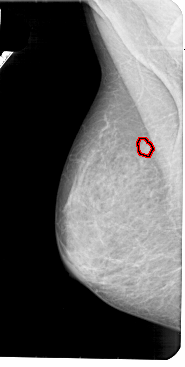

A_1947_1.LEFT_CC

LEFT_CC LINES 5356 PIXELS_PER_LINE 2806 BITS_PER_PIXEL 12 RESOLUTION 43.5 OVERLAY

FILE: A_1947_1.LEFT_CC.OVERLAY

TOTAL_ABNORMALITIES 1

ABNORMALITY 1

LESION_TYPE MASS SHAPE ROUND MARGINS CIRCUMSCRIBED

ASSESSMENT 3

SUBTLETY 4

PATHOLOGY BENIGN

TOTAL_OUTLINES 1

BOUNDARY